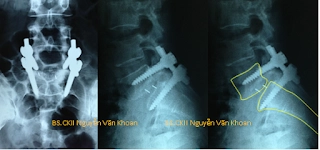

Hình X quang cho thấy bệnh nhân bị trượt đốt sống thắt lưng L5/S1 đã được mổ nắn chỉnh, đặt dụng cụ ốc chân cung với 2 thanh nối dọc, hàn liên thân đốt bằng nêm PEEK.

Có nhiều phương pháp mổ để điều trị trong trường hợp này. Phẫu thuật nắn chỉnh trượt, đặt dụng cụ, hàn xương liên thân đốt lối sau cho kết quả tốt và được làm nhiều nhất hiện nay, tuy nhiên dụng cụ lại đắt tiền.

Việc nắn chỉnh là cần thiết để sửa sự biến dạng tư thế xấu cho bệnh nhân. Cố định bằng dụng cụ và hàn xương giúp giữ sự vững chắc cho cột sống về sau. Song song với việc nắn chỉnh, hàn xương và cố định dụng cụ thì việc giải ép rễ thần kinh là cần thiết.

Phẫu thuật nắn chỉnh trượt, cố định ốc chân cung, hàn liên thân đốt lối sau là phẫu thuật được cho là hiệu quả nhất hiện nay để điều trị trượt đốt sống thắt lưng. Bệnh nhân cần chú ý, có 3 vấn đề hết sức cơ bản trong phẫu thuật điều trị trượt đốt sống, giúp cuộc mổ thành công, đó là: